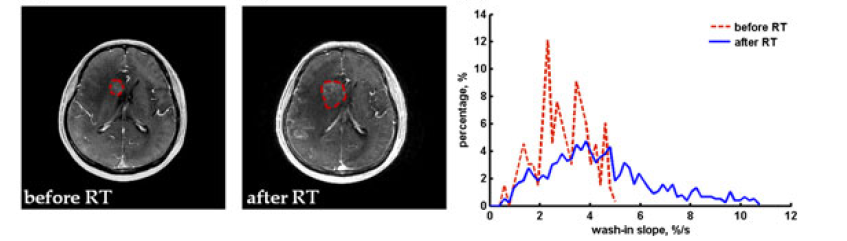

图1 影像组学研究的流程 影像组学在研究中的应用 影像组学已经被广泛用于对不同疾病病灶的研究,其中以肿瘤病灶研究较多。影像组学不仅可以从形态学和纹理角度来揭示肿瘤的形态,同时它在肿瘤临床应用中有很大的潜力。例如影像组学对放化疗评估,肿瘤分级,良恶性辨别以及基于基因的肿瘤分类上都有着较强的预测能力,下文姜从几个方面给出临床上影像组学的若干应用。 放化疗的疗效评估预测应用 放化疗的疗效评估是衡量治疗方案,评估临床决策的有效手段,这里我们介绍一些常见的利用影像组学中的特征来进行疗效评估的应用。很多研究给出了MR在放化疗效评估中,使用基于直方图(histogram-based feature)特征的影像组学方法给出较高预测率的实例,如图2所示的一例脑肿瘤的放疗疗效评估研究中,文章使用MRI动态增强图像,结合DCEMRI分析方法,比较了治疗前后的血液动力学参数和直方图参数的相关性和差异,图中可见治疗前后的直方图和峰度(kurtosis)具有较强相关性。

图2 肿瘤治疗前后定量分析 同时在动物实验中,使用临床前模型对患有恶性肉瘤的小鼠进行ADC图像的扫描,发现治疗前后肿瘤区域ADC值的直方图特征,如偏度(skewness),峰度(kurtosis),熵(entropy)均有显著性的差异;利用直方图参数评估头颈部肿瘤的放化疗效果过程中,较差疗效结果相对良好的放化疗效,其ADC图像中肿瘤部位往往呈现较高的峰度和偏度值;同时也有研究将DCEMRI血液动力学模型计算的参数-KTrans作为特征计算的图像,其中KTrans的偏度(Skewness)被发现可以作为中晚期头颈部肿瘤的整体存活率的有效评估依据。 肿瘤细胞分化程度研究 肿瘤细胞分化程度的研究在在临床中具有很重要的意义,它可以提供给临床诊疗决策和影响治疗方案的制定,这里我们也介绍若干影像组学在肿瘤分级上的应用。以往的众多研究中显示,影像组学的特征对早期和较晚期的肿瘤表现出良好的分辨能力,例如在基于PET图像的食管癌分级研究中,SUV-max,Entropy,energy都在辨别早期和中晚期肿瘤中具有显著性的差异,尤其是熵(entropy)达到一定阈值后对鉴别二期肿瘤有着相关性较高的结果;同时有研究发现,在宫颈癌的分级研究中,基于PET图像的步长矩阵纹理特征(RLM)可以很好的鉴别早期肿瘤(I,II期)和晚期肿瘤(III,IV期);在肺癌分级研究中,基于CT图像的高斯滤波纹理特征对鉴别II期以上的肿瘤有着良好的分辨能力。 肿瘤良恶性辨别应用 影像组学中的特征可以在很多临床应用中鉴别肿瘤的良恶性(见图3),从而可以对临床的决策起到指导作用。上世纪90年代,有研究报告基于灰度共生矩阵(GLCM)的纹理特征在分析二维的T1,T2 MRI图像时,可以通过GLCM的到的参数辨别脑部各个区域的肿瘤良恶性;除了组学参数在脑部的应用,在其他部位例如乳腺肿瘤的良恶性辨别上,影像组学也有非常多的应用,例如08年的一例研究中,研究者结合基于形状的纹理参数(shape-based),共生矩阵纹理参数(GLCM)以及三维纹理(volume),利用人工神经网络(ANN)作为训练方法,得到了鉴别率较高的乳腺肿瘤良恶性辨别模型,下图表示了基于直方图(Histogram)的参数 - Gray Level Sum Average对乳腺肿瘤良恶性辨别的例子,蓝色的区域表示良性的肿瘤分布在level较低的区域,红色区域表示恶性的区域。